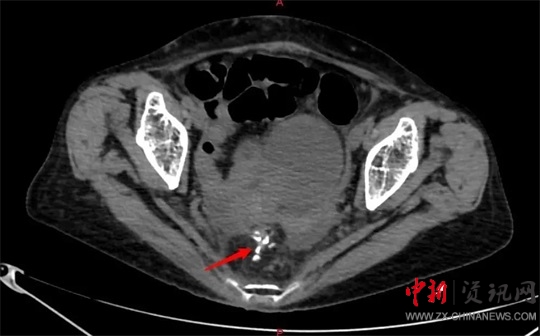

劉大勇對(duì)侯老太太進(jìn)行仔細(xì)的體格檢查及相關(guān)的影像學(xué)檢查后,考慮患者已經(jīng)急性直腸穿孔,且出現(xiàn)了血壓下降、心率增快、脈搏細(xì)弱等休克癥狀,就迅速把侯老太太的病情匯報(bào)給了胃腸外科、疝與腹壁外科主任廖新偉。當(dāng)晚8點(diǎn)左右,廖新偉立即組織科室進(jìn)行會(huì)診。大家一致認(rèn)為患者病情危重,隨時(shí)可能出現(xiàn)生命危險(xiǎn),急診手術(shù)刻不容緩。

當(dāng)晚9點(diǎn)40分,廖新偉積極協(xié)調(diào),麻醉科手術(shù)部及輸血科密切配合,以劉大勇主刀、副主任醫(yī)師汪麗偉輔助,緊急為侯老太太施行了手術(shù)。打開(kāi)腹腔,驚人地發(fā)現(xiàn)侯老太太腹腔已被糞便填滿,腸子漲的像氣球那么大。術(shù)中,經(jīng)過(guò)沖洗并且減壓腸道后,醫(yī)護(hù)團(tuán)隊(duì)在直腸上段發(fā)現(xiàn)一大小約1.5cm破口,一堅(jiān)硬物嵌頓在破口處,打開(kāi)腸壁,一排帶鉤的假牙映入眼前。醫(yī)護(hù)人員將假牙小心翼翼地完整取出,足足有4cm長(zhǎng)。由于侯老太太腹腔污染嚴(yán)重,且腸梗阻時(shí)間較長(zhǎng),腸壁水腫十分嚴(yán)重,無(wú)法再次重建消化道,于是胃腸外科團(tuán)隊(duì)給老太太做了直腸遠(yuǎn)端封閉+乙狀結(jié)腸造口術(shù)?紤]到患者腹腔污染術(shù)后可能出現(xiàn)感染腹腔膿腫等情況,醫(yī)護(hù)團(tuán)隊(duì)給侯老太太左右上下總共放了5根引流管。